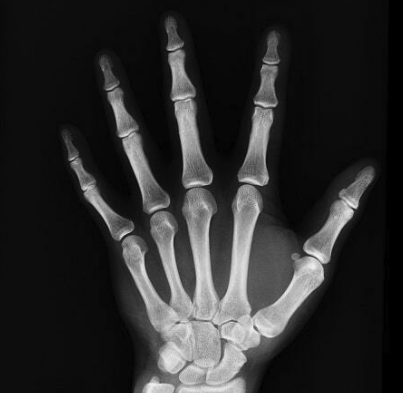

Fraxpert is an AI-supported fracture diagnostic system to deliver fast and accurate plain film interpretation. Radiologists and A&E clinicians are exhausted and overworked. Fraxpert aims to bridge the gap between supply and demand for image diagnostic interpretation, so that patients receive their correct diagnosis at the first point of consultation and radiologists never have to work outside their contracting hours.

Confident Fracture Detection

Fraxpert aims to support radiologists and frontline clinicians by confidently confirming the presence or absence of fractures in x-ray images, the same way as expert radiologists.